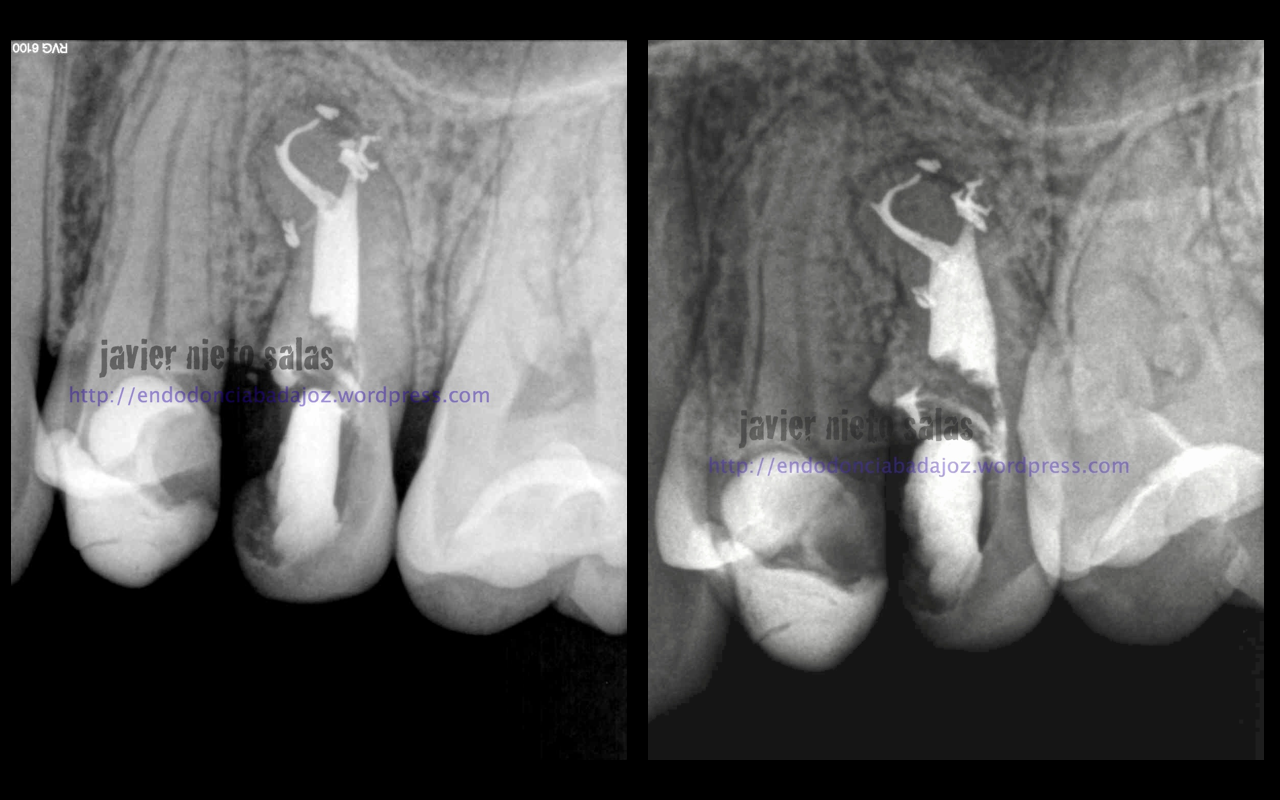

Este segundo caso, después de estudiar la Rx, vemos un defecto en la furca, y ¿porqué no puede ser el origen las endotoxinas y demás productos de las bacterias intraconducto que colonizan un conducto lateral en ese nivel medio? ( 15% según Vertucci)